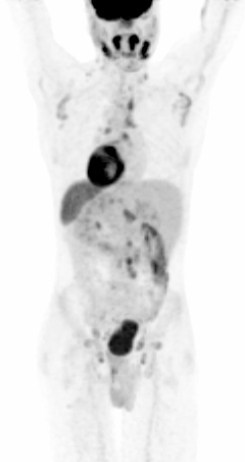

PREPARING MY PATIENT FOR F-18 FDG PET/CT STUDY